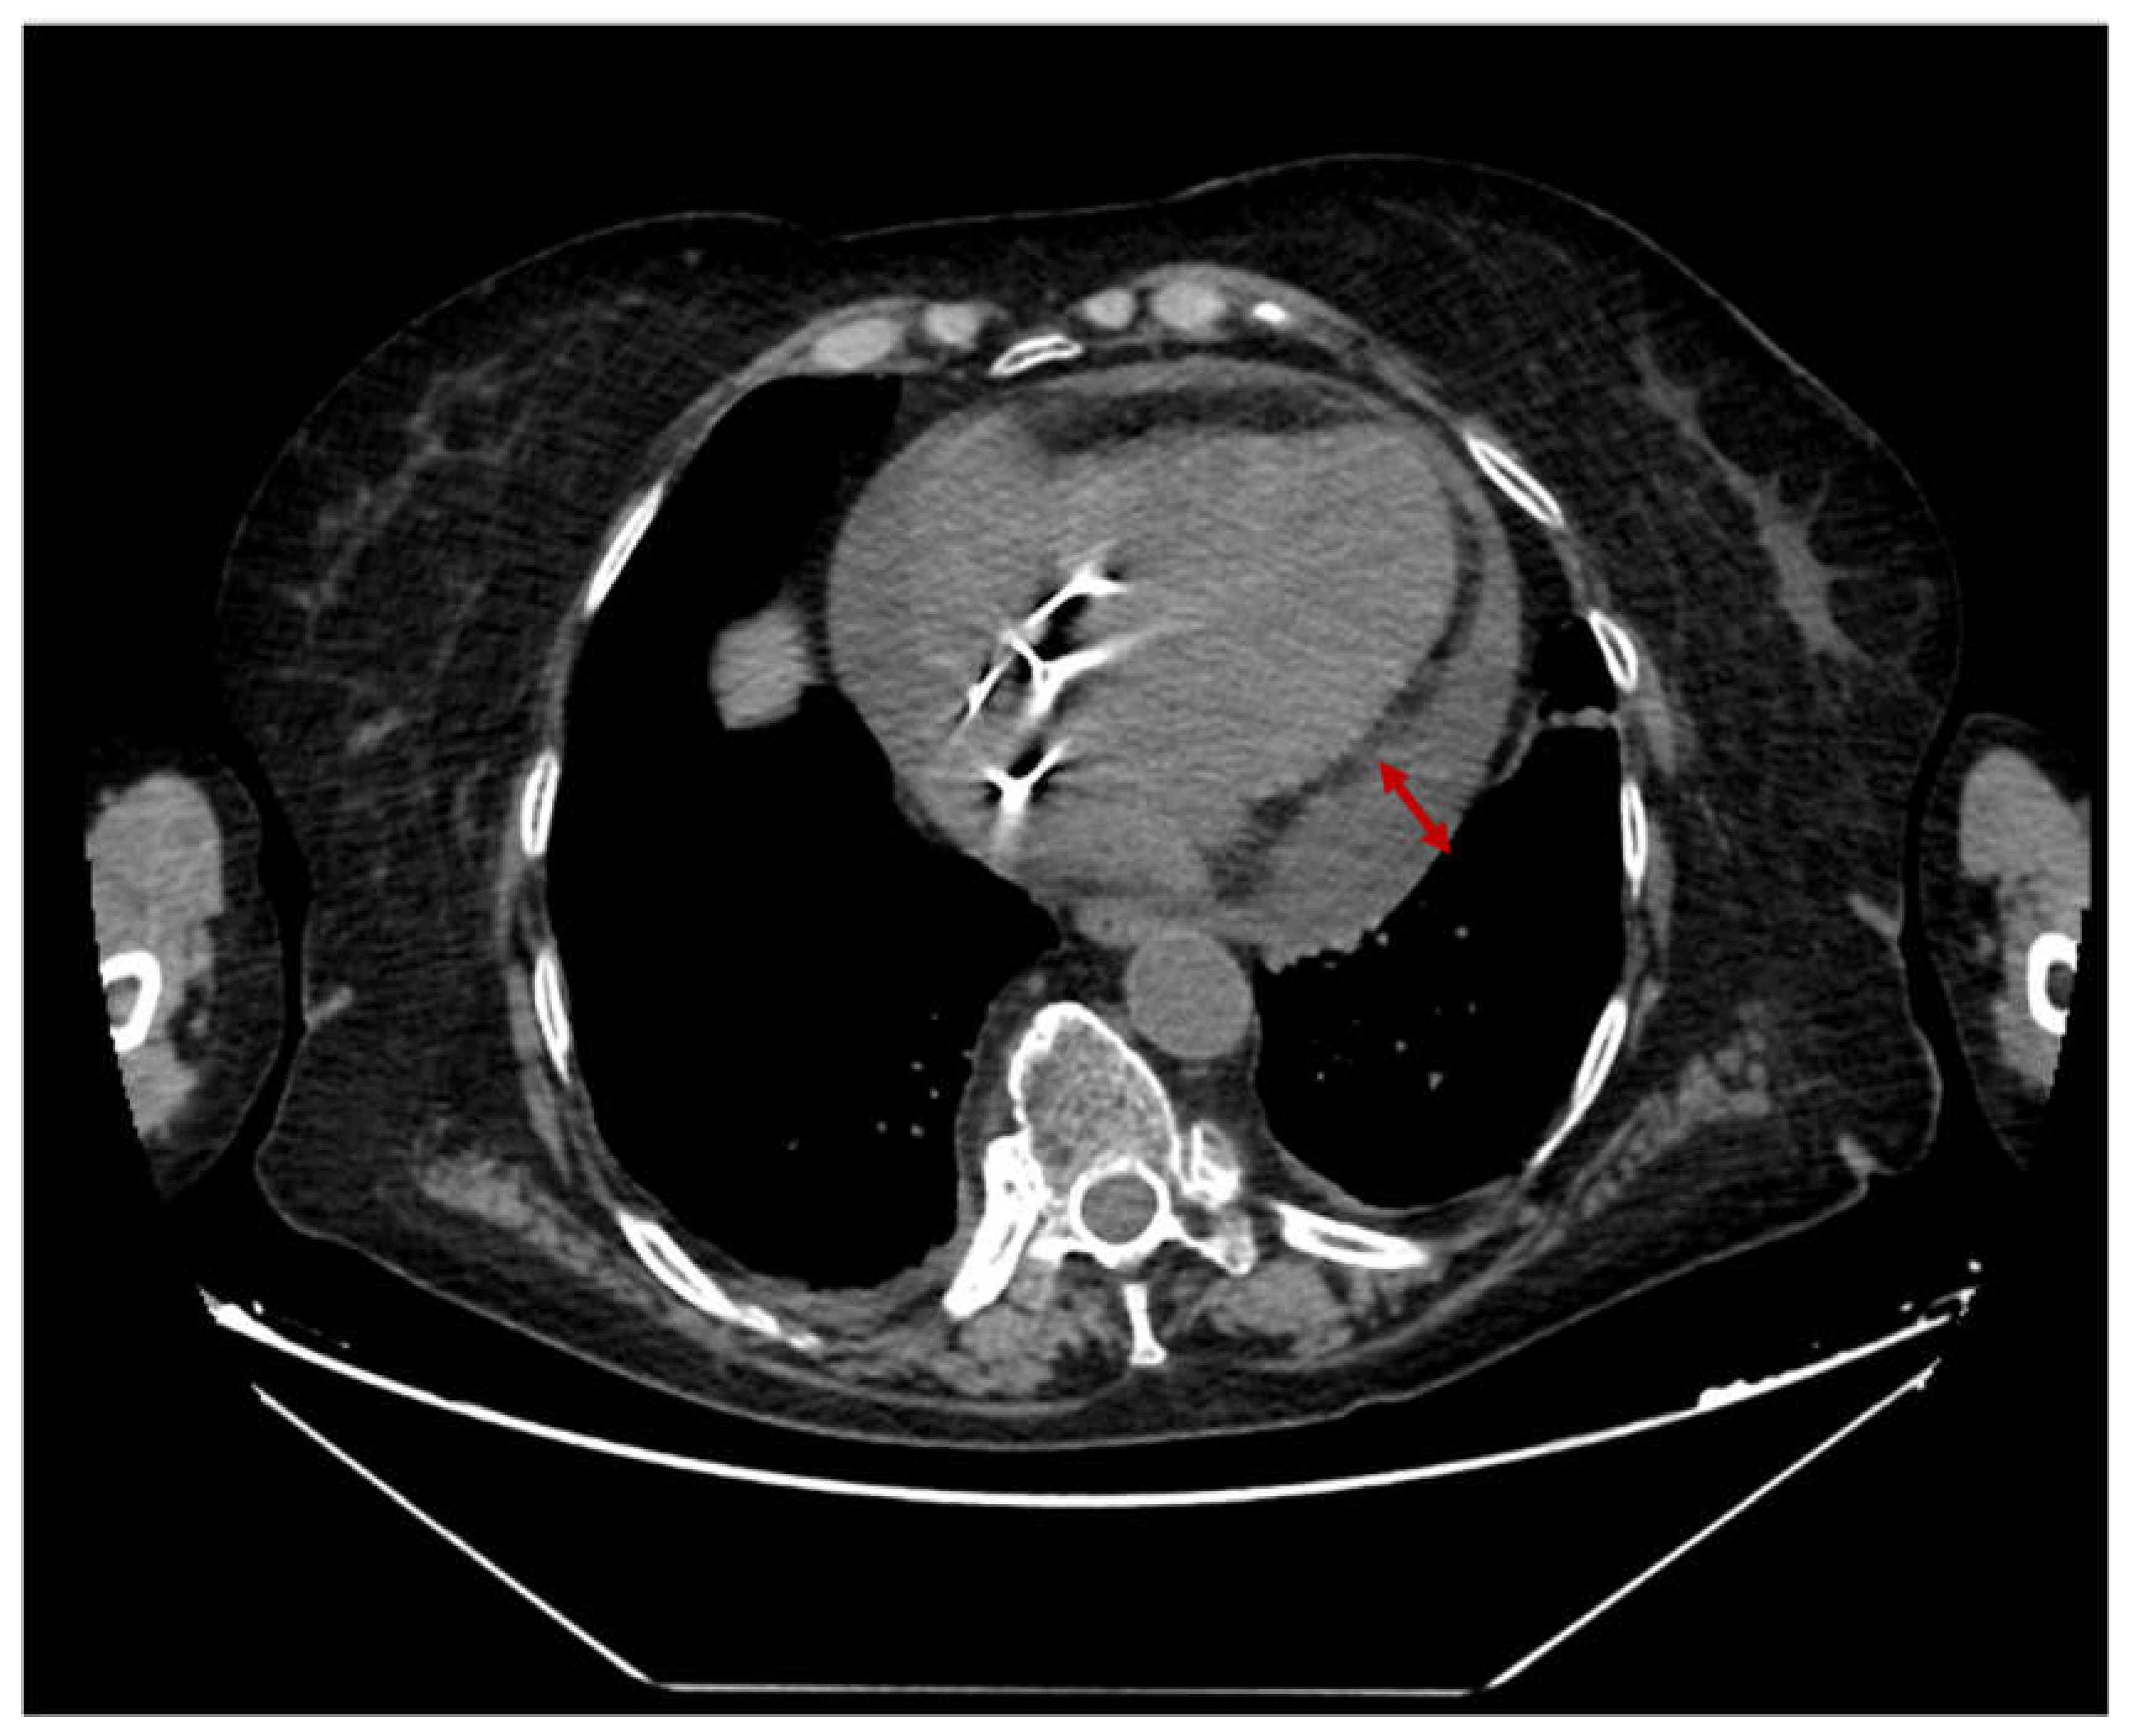

2.2. Case 2